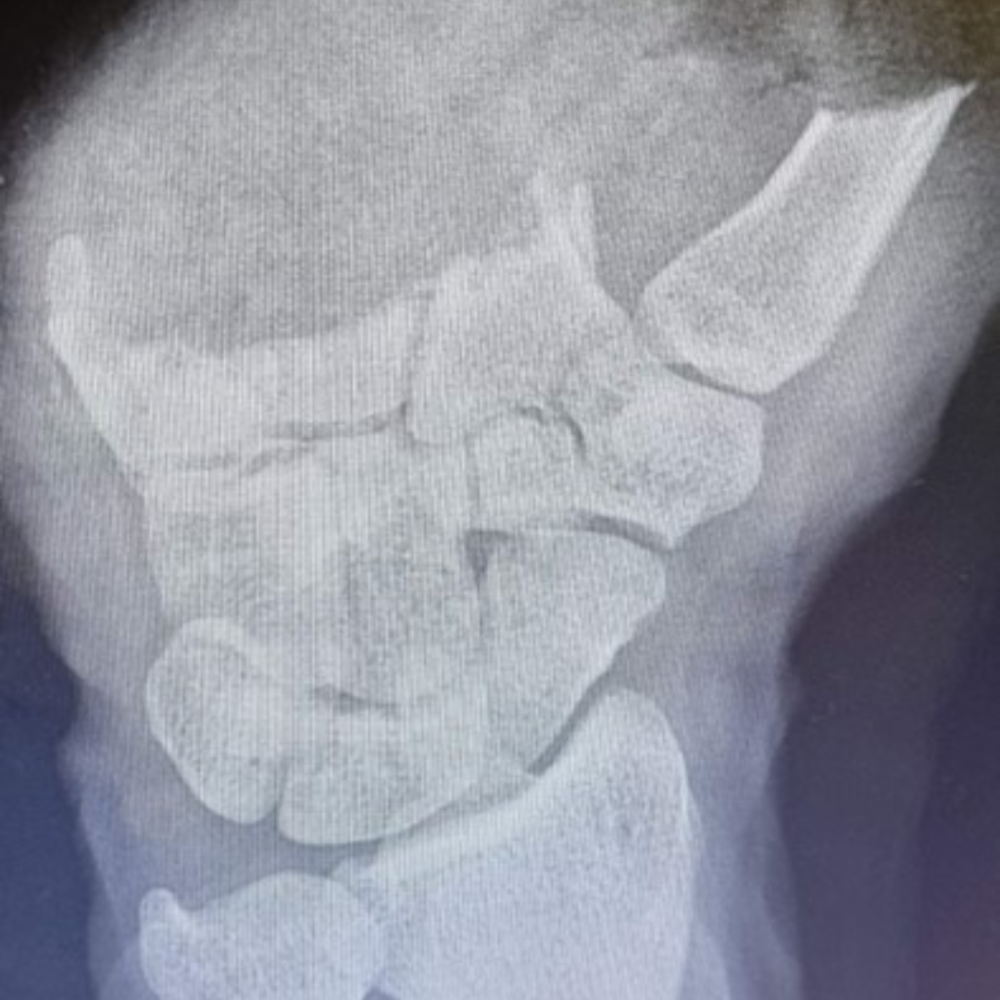

W ciągu prawie 2 lat działalności, oprócz regularnych dyżurów, wykonano również ponad 10 replantacji poza grafikiem. Jest to o tyle szczególna sytuacja, że do zabiegu znaczna część personelu przyjeżdża z domu w swoim wolnym czasie, po to, by pomóc uniknąć pacjentowi ciężkiego kalectwa po amputacji. Takie „pospolite ruszenie” zdarza się głównie wtedy gdy w grafiku „serwisu” nie ma zgłoszonego ośrodka lub pacjentów po urazie amputacji w danym dniu jest więcej niż ośrodków, które dyżurują. Do najczęściej przeprowadzanych zabiegów w ciągu roku działalności 5WSzKzP w „serwisie replantacyjnym” należały: replantacje palców  (głównie kciuka), rewaskularyzacje (niepełne amputacje ale wymagające pilnego szycia naczyń) oraz ciężkie wielotkankowe urazy ręki. W trakcie prawie 2 letniej działalności wykonano około 50 takich procedur.